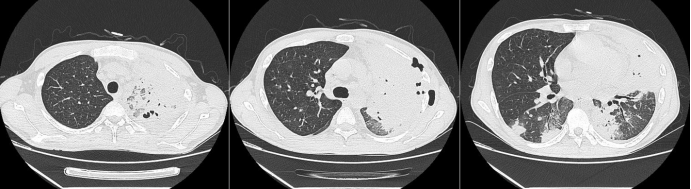

患者在伏立康唑及卡泊芬净联合治疗的情况下,仍然出现影像学进展,考虑治疗效果不佳。从病原学相关因素、宿主相关因素、药物相关因素等三方面进一步明确治疗效果不佳原因。

首先进一步明确病原学,排除其他感染可能,于2021年10月15日予行肺穿刺。